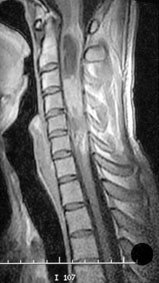

Eine weitere Nachbehandlung bei kompletter Tumorentfernung des benignen Ependymoms musste nicht durchgeführt werden, und der Patient kann als geheilt erachtet werden. Auf Grund einer sehr seltenen Rezidivrate muss jedoch eine mehrjährige Nachkontrolle mittels MRI durchgeführt werden (Bild 3).